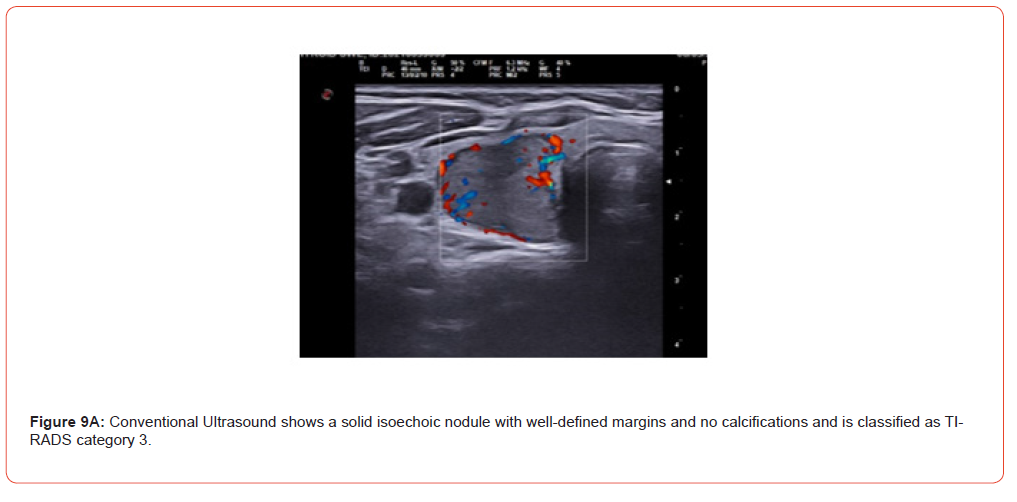

Figure 9 and 10 show representative case of benign and malignant thyroid nodule.